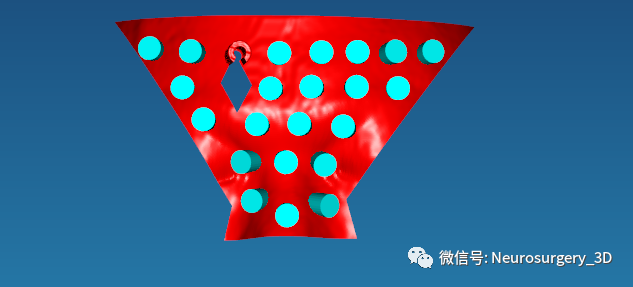

11、穿刺导板镂空:把Mimics剪切后的导板导入E3D软件界面,进行镂空处理后备用。